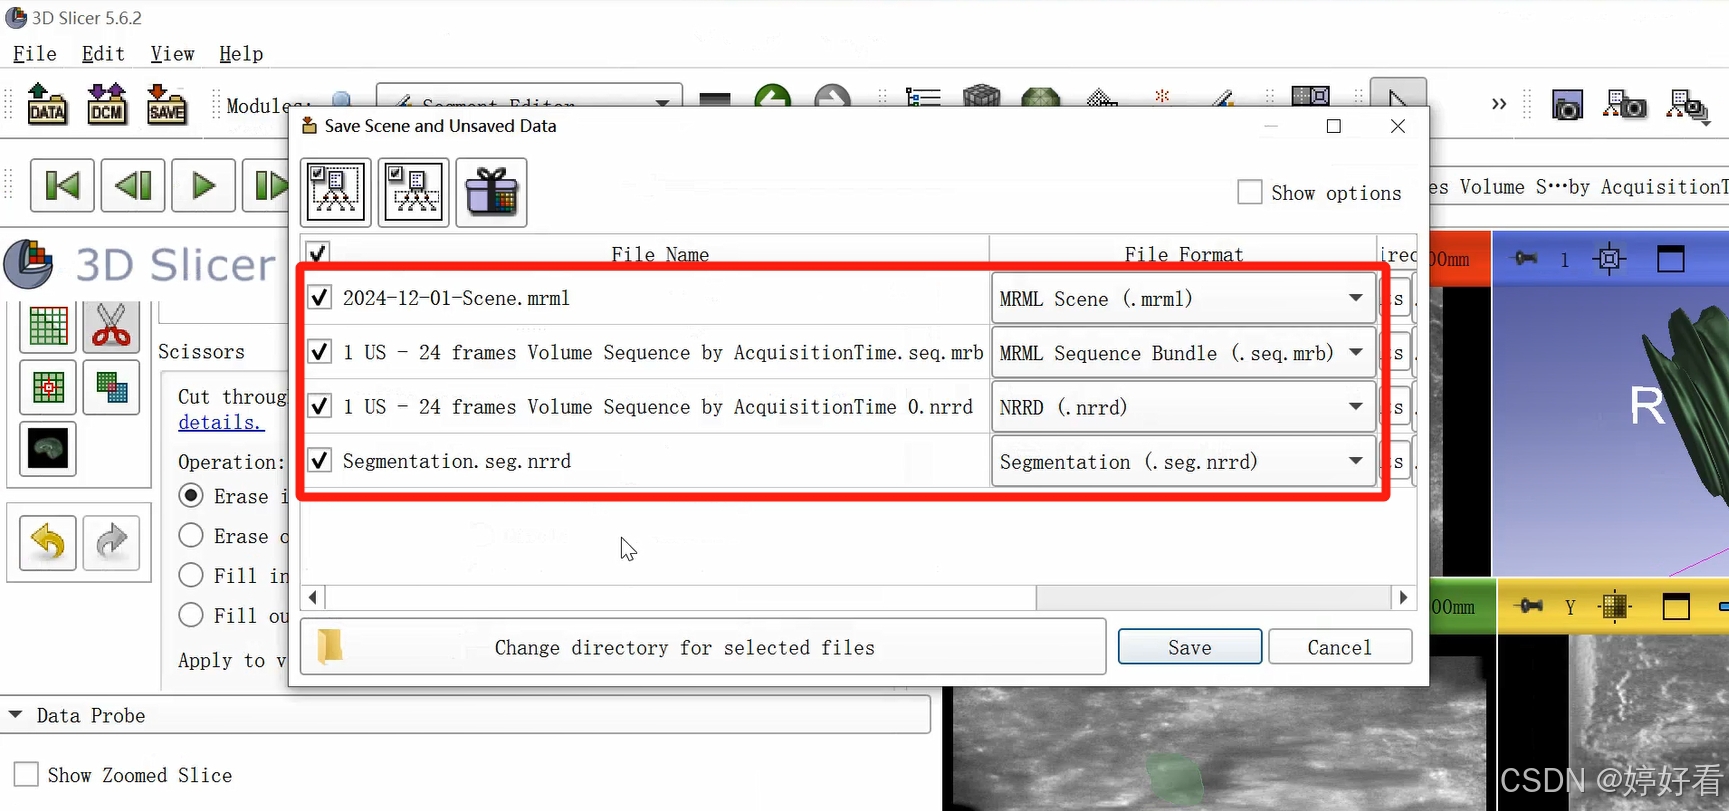

3、 保存

点击“Save”,弹出的对话框包含4个文件,其中2个是分割前的原始文件,另外2个是分割后的文件。